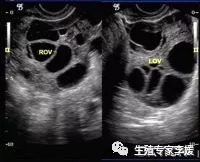

1.超声的误差:窦卵泡的直径仅为2~5mm,不同的机器、不同的切面以及不同医生看到的窦卵泡数可能不同。直径较小的窦卵泡可能会看不到,而卵巢内的小血管、小囊肿也可能会被误认为是窦卵泡。